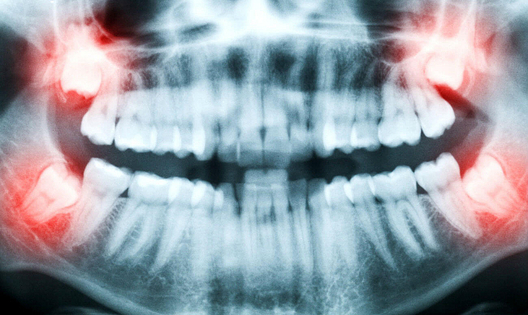

Мы працягваем публікаваць парады сківічна-тваравага хірурга, якія, магчыма, будуць карысныя нашым чытачам. Гэтым разам яны тычацца выдалення зуба пры алергіі.

Усё часцей паліклінікі выносяць пацыентам прысуд «полівалентная алергія» і выпраўляюць выдаляць зубы ў стацыянар. Наколькі гэта абгрунтавана, ці ёсць рызыка насамрэч, як з гэтым разабрацца і не сапсаваць здароўе на пустым месцы.